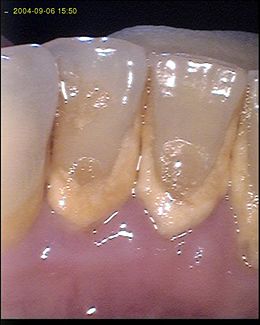

| Fig.2. Periodontite |

Uma vez estabelecida a gengivite, pode manter-se como tal durante uns dias, meses ou anos. Se não for tratada, com a eliminação bacteriana, a gengivite não cura espontâneamente. Se for tratada, a sintomatologia desaparece e restabelecem-se as condições que existiam antes da doença sem sequelas. No entanto, na maioria dos indivíduos, em muitos pontos do periodonto a gengivite transforma-se em periodontite, quando o infiltrado inflamatório gengival ultrapassa a barreira defensiva formada pelas fibras gengivais. A razão pela qual sucede, e quando sucede não pode ser determinada, mas podemos suspeitar de várias razões:

- Aumento da virulência bacteriana;

- Diminuição das defesas do hospedeiro;

- Destruição mecânica, intencional ou não, ao nível da união dento-gengival (invasão do espaço biológico).